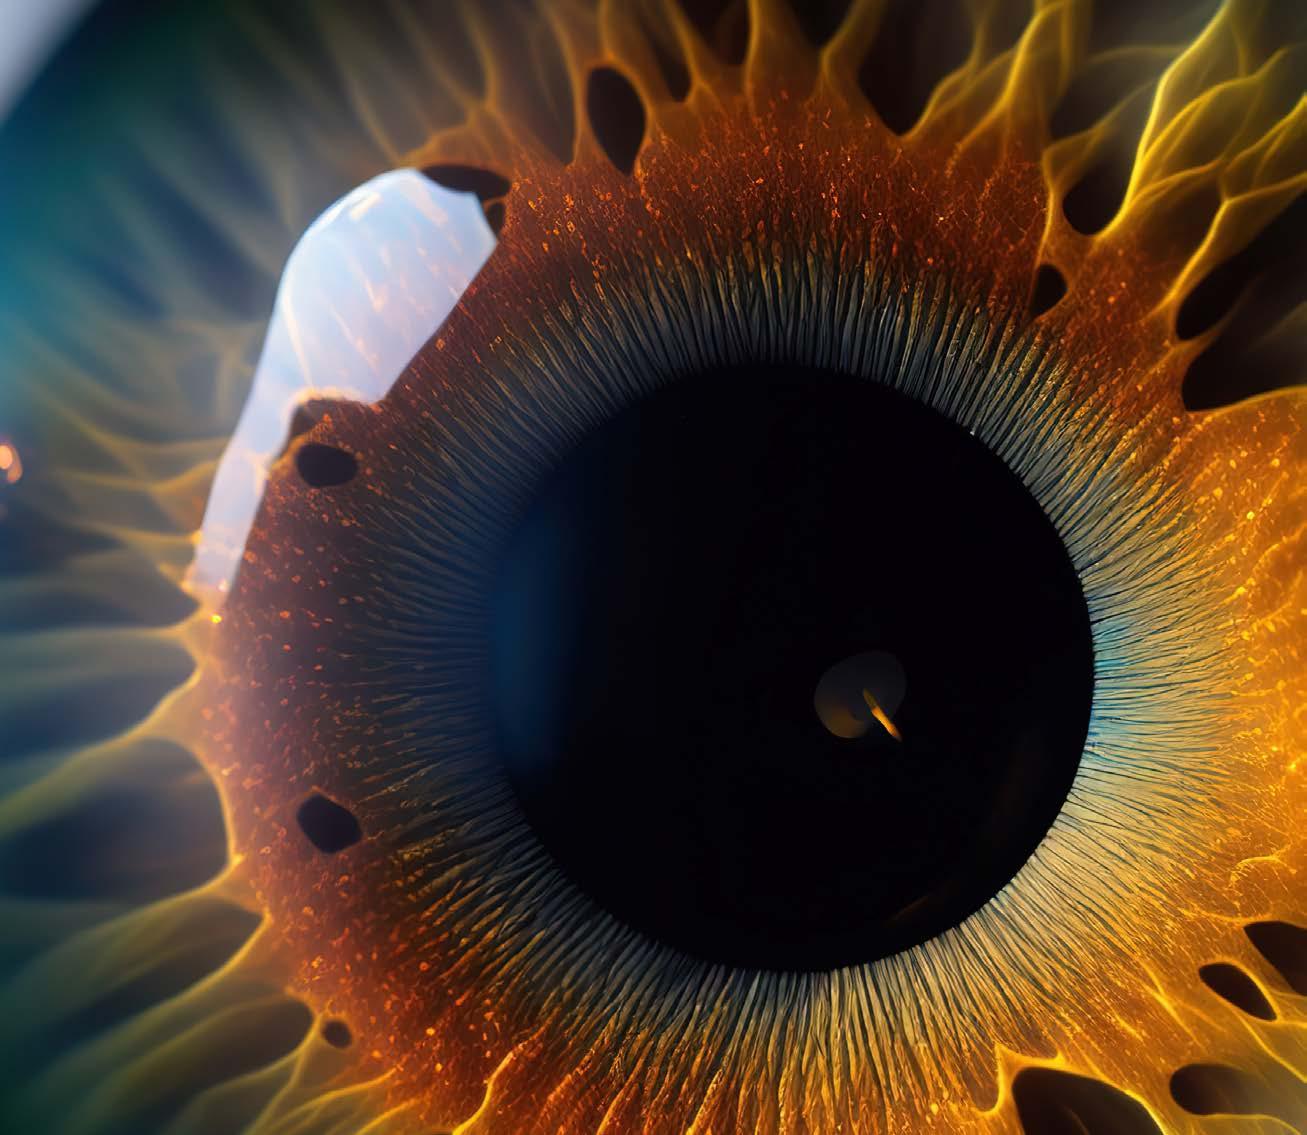

Intraocular lenses are not all alike; they can differ in many aspects. “Different IOL materials can have different characteristics in terms of surgical outcomes, quality of vision, flexibility, and especially biocompatibility and interaction with the ocular tissues,” said Tiago Monteiro, MD, PhD, FEBOSCR.

During his presentation in Copenhagen, Dr Monteiro noted that intraocular lenses can be divided into acrylic hydrophobic, acrylic hydrophilic, and acrylic hydrophilic with hydrophobic surface properties. Acrylic hydrophobic lenses are acrylic with low water content, so they have a higher contact angle and less surface wettability, Dr Monteiro said. Surface wettability is clinically relevant because it influences protein and cell adhesion to the lens.

Hydrophobic lenses are thinner, Dr Monteiro noted, meaning there is a higher level of flexibility in higher-power IOLs. Hydrophobic lenses also bring a lower incidence of posterior capsule opacification, therefore lowering the rates of YAG laser capsulotomy procedures. Moreover, Dr Monteiro said, there is a lower risk of IOL opacification and calcification.

Hydrophobic lenses, on the other hand, come with some problems, mainly surface haze, glistening and nanoglistening, micro- and nanovacuoles of water that come up from the separation of water inside the polymer of the IOL. According to Dr Monteiro, different hydrophobic acrylic IOLs exhibit varying susceptibilities to glistening formation, reflecting differences in copolymer composition and manufacturing techniques. This created a clinical demand that pushed the industry to search for viable alternatives that can lower the incidence of glistening in their models of hydrophobic IOLs.

Acrylic hydrophilic lenses have a higher water content, with a higher surface wettability and lower contact angles. This results in fewer adhesions inside the capsular bag, making them theoretically easier to detach from the bag in case of a lens explantation, Dr Monteiro said.

Hydrophilic lenses have a lower refractive index and, therefore, less surface reflection. The lens doesn't shine inside the patient's eye, so patients with hydrophilic lenses normally don't have the “cat’s eye effect” that can be seen in some hydrophobic lenses, Dr Monteiro said. These lenses, however, have a higher incidence of posterior capsular opacification (PCO) and consequentially higher rates of Nd:YAG laser capsulotomies, as well as higher risk of IOL opacification and calcification.

Opacification in hydrophilic lenses have been described as primary, in cases of calcium buildup inside the lens due to fabrication and packaging issues, or secondary—which is much more frequent—where there is calcium showing on the outer surface of the lens. This is normally due to clinical factors related to the patient (glaucoma and diabetes are risk factors) or procedures like DSAEK, DMEK and pars plana vitrectomy that use gas or air. Dr Monteiro recommended that hydrophilic lenses be avoided in patients with diabetes, glaucoma and uveitis, as well as in patients with a higher risk of developing PCO. “There are patients with Fuchs dystrophy, for instance, or patients with whom you are planning to do some kind of endothelial keratoplasty with the use of gas or air,” he said.